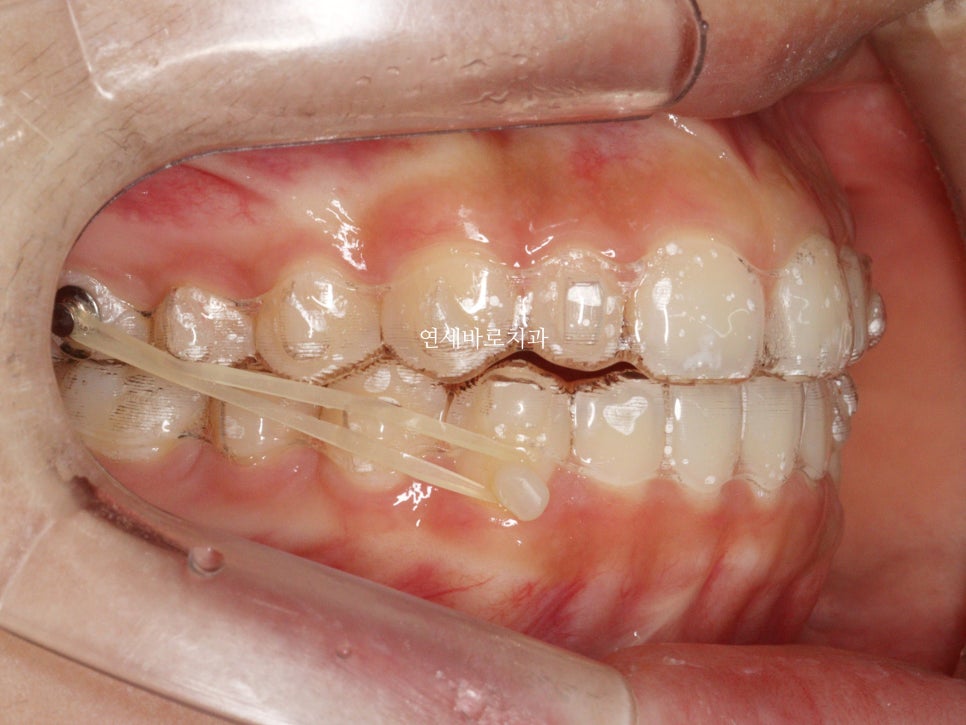

이 환자분도 중심선을 맞추기 위해 고무줄을 함께 사용했습니다.

- Invisalign Lite treatment with rubber bands for midline correction